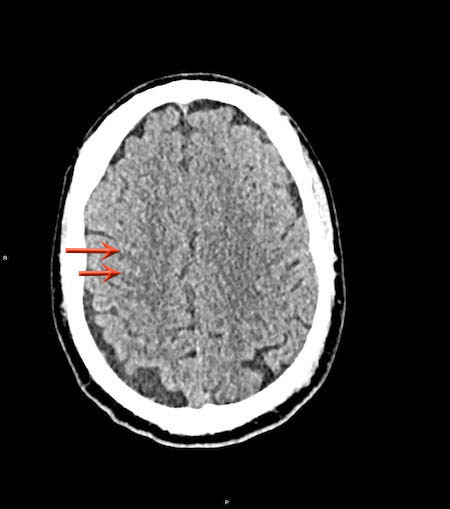

Tụ máu dưới màng cứng đồng tỷ trọng

Khi tụ máu dưới màng cứng tiến triển theo thời gian, tỷ trọng của khối tụ máu sẽ giảm dần và có thể tương đương với tỷ trọng của nhu mô não, khiến việc phát hiện tổn thương trở nên khó khăn.

Đây là trường hợp tụ máu dưới màng cứng đồng tỷ trọng rất khó phát hiện (các mũi tên).

Lưu ý rằng ở mức cắt cao hơn có tụ máu dưới màng cứng hai bên.